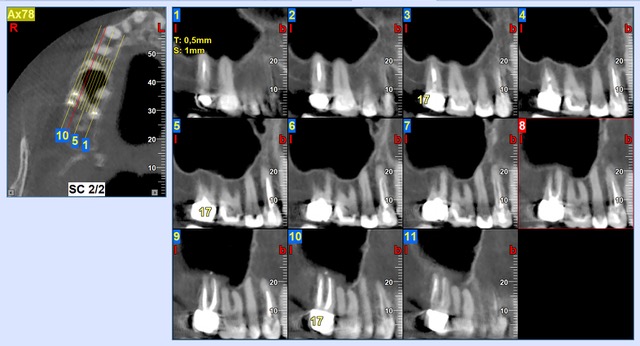

Ik heb nog een aantal afbeeldingen van de scan online gezet, en een overzichtsfoto, die een paar maanden na de WKB is gemaakt. >>http://3dscan.jalbum.net/x-ray-scan/<<

Daarmee is ze naar de kaakchirurg geweest omdat de tandarts dacht aan een kaakholte ontsteking. Hoe dit verder is verlopen moet ik ook even op een rijtje zetten.

de foto's zijn van okt/nov 2020 en de cbct van juni 2021.

Welke kroon is als laatste geplaatst?. Als het de 16 is dan zou ik op basis v d tweede foto zien dat aan een v d mesiale ( voorste wortel) een ontsteking is. Excuseer als ik het fout zie, ik moet het doen met wat u mij levert. Wortelpunt v d 14 is voor mij ook verdacht. Koud en warm alleen in die kies of meerdere, dat is verwarrend maar kan verklaard worden doordat een kanaal "dood" is en de andere nog niet. Ik zou in de 16 proefboren zonder verdoving. Als er geen gevoel in is dan een wortelkanaal behandeling. Maar als er toch gevoel in zit geeft dat geen uitsluitsel. Ik zou beginnen met een WKB in de 16. U bent overal geweest zegt u. Wat was het oordeel v d endodontoloog.